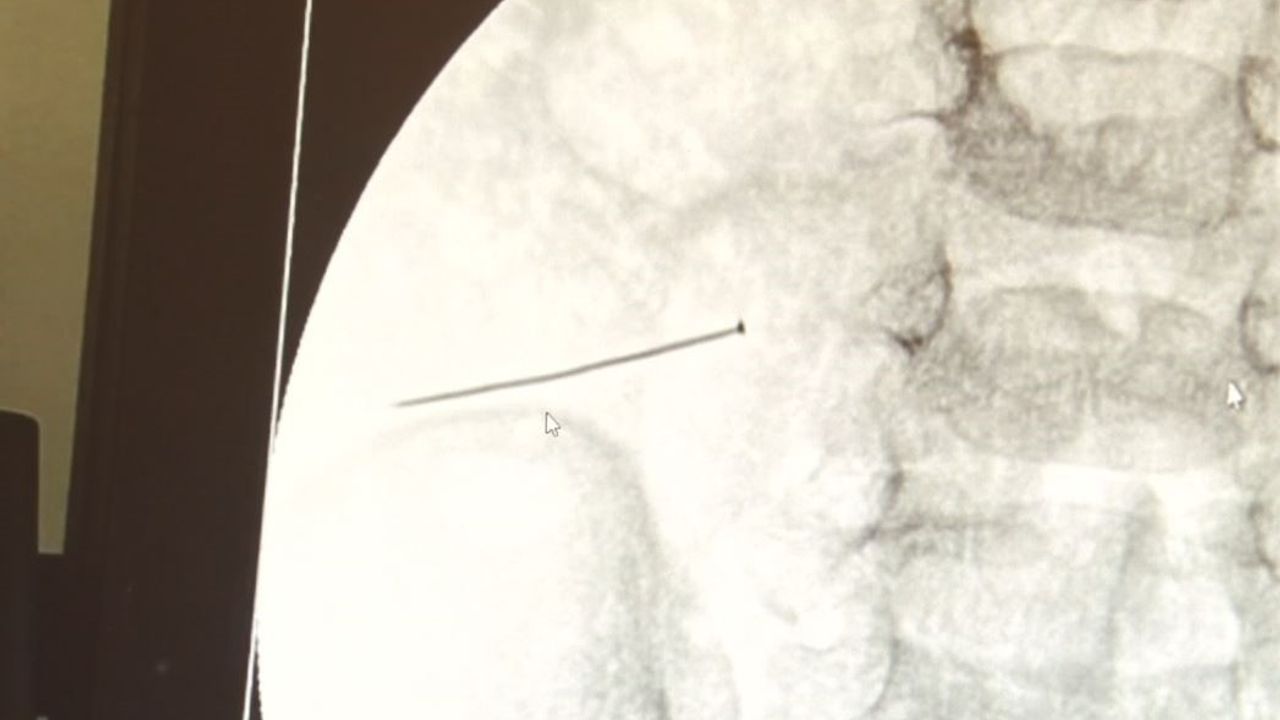

Öte yandan, yaklaşık 3 santimlik toplu iğne filme yansıyan görüntüsüyle gözler önüne serildi.

"Soluk borusuna kaçması durumunda çocuğun Allah göstermesin ölümüyle veya ömür boyunca yatağa bağımlı kalmasıyla neticelenebilecek sonuçlar doğurabiliyor. Yutulması durumunda da gastrointestinal sistemin herhangi bir yerine takılmadığı müddetçe ekseriyâ yabancı cisimlerin dışarıya çıkmasını bekliyoruz. Yabancı cisim yutulmasını 2 grupta inceleyebiliriz. Sıvı ve katı cisimler olarak sıvı; evde kullanılan kimyasal temizlik malzemelerinin yutulması çok ciddi problemler oluşturabilmekte. Ağızda, yemek borusunda ve midede yanıklar meydana getirebilmekte. Uzun dönemde çocukların hayat kalitesini oldukça etkileyen sonuçlar doğurabilmekte. Katı cisimlerden de ekseriyâ kendiliğinden çıkmasını bekleriz ancak böyle delici, kesici aletlerin yutulmasında ise herhangi bir bağırsağın veya gastrointestinal sistemin bir parçasında delinmeler meydana getirebiliyor. Bu çocuğumuzda da aynen böyle bir hadise meydana gelmişti. Sanırım 1 gün önce ailenin yuttuğunu tahmin ettiği bir yabancı cisim; toplu iğne. Ertesi gün bağırsakta delinmeyle sonuçlanmış ve çocukta da ciddi semptomlar meydana getirmişti. Bu şekilde hasta bize başvurdu. Tetkikler sonucunda yabancı cismi tespit ettik, semptomları ve bulgularına göre de çocuğu ameliyata aldık. Yaklaşık 3 santim boyunda bir toplu iğnenin ince bağırsağı deldiğini, ince bağırsaktaki içeriğin de karın içerisine dolduğunu gördük. Ameliyatı başarılı bir şekilde tamamladık, yaklaşık 1 saat süren bir ameliyattı."